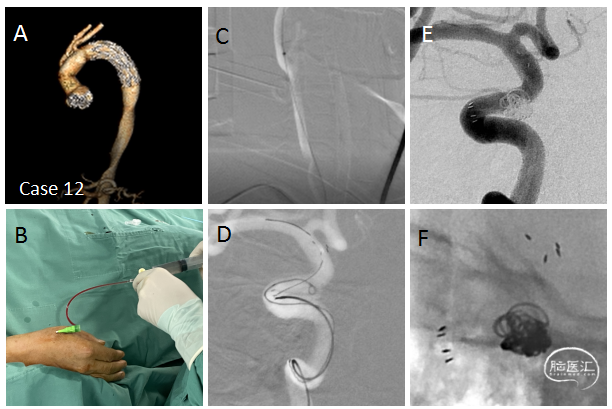

病例12

经远侧桡动脉治疗眼动脉动脉瘤(既往主动脉弓夹层行人工弓置换术后股动脉入路不能,三型弓,右侧锁骨下动脉和颈总动脉僵硬30度锐角),经远侧桡动脉入路顺利栓塞动脉瘤。